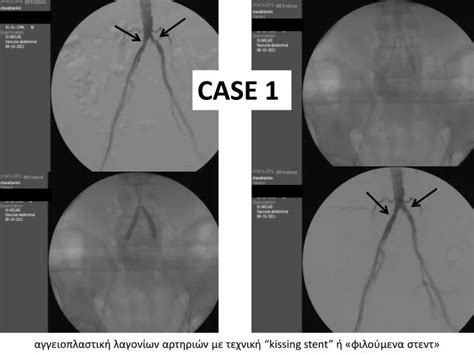

So, what can you expect if you’re going in for a kissing stent procedure ? Don’t worry, it’s generally a minimally invasive process. First off, you’ll likely be given some medication to prevent blood clots and keep you comfortable. The procedure is typically performed while you’re awake, but you’ll receive sedatives to help you relax. The access point is usually in your groin or wrist, where a small incision is made. A thin, flexible tube called a catheter is then guided through your blood vessels, all the way to the blocked area in your heart. Real-time X-ray imaging (fluoroscopy) is used to guide the catheter precisely. Once the catheter is in place at the bifurcation, the interventional cardiologist will deploy tiny balloons to confirm the blockage and prepare the area. Then, the kissing stent procedure really begins. Two stents, mounted on balloon catheters, are carefully positioned. One stent goes into the main artery, and the other goes into the side branch. The balloons are inflated, expanding the stents against the artery walls, and then withdrawn. Sometimes, a final inflation of a balloon is done across both stents to ensure they are well-apposed and open. The whole process usually takes a couple of hours. It’s a highly skilled procedure, focusing on restoring optimal blood flow to both the main vessel and the crucial side branch. The minimal invasiveness means a quicker recovery compared to open-heart surgery. Your medical team will be monitoring you closely throughout, ensuring your safety and comfort every step of the way. They’ll explain everything as it happens, so you’re always in the loop.